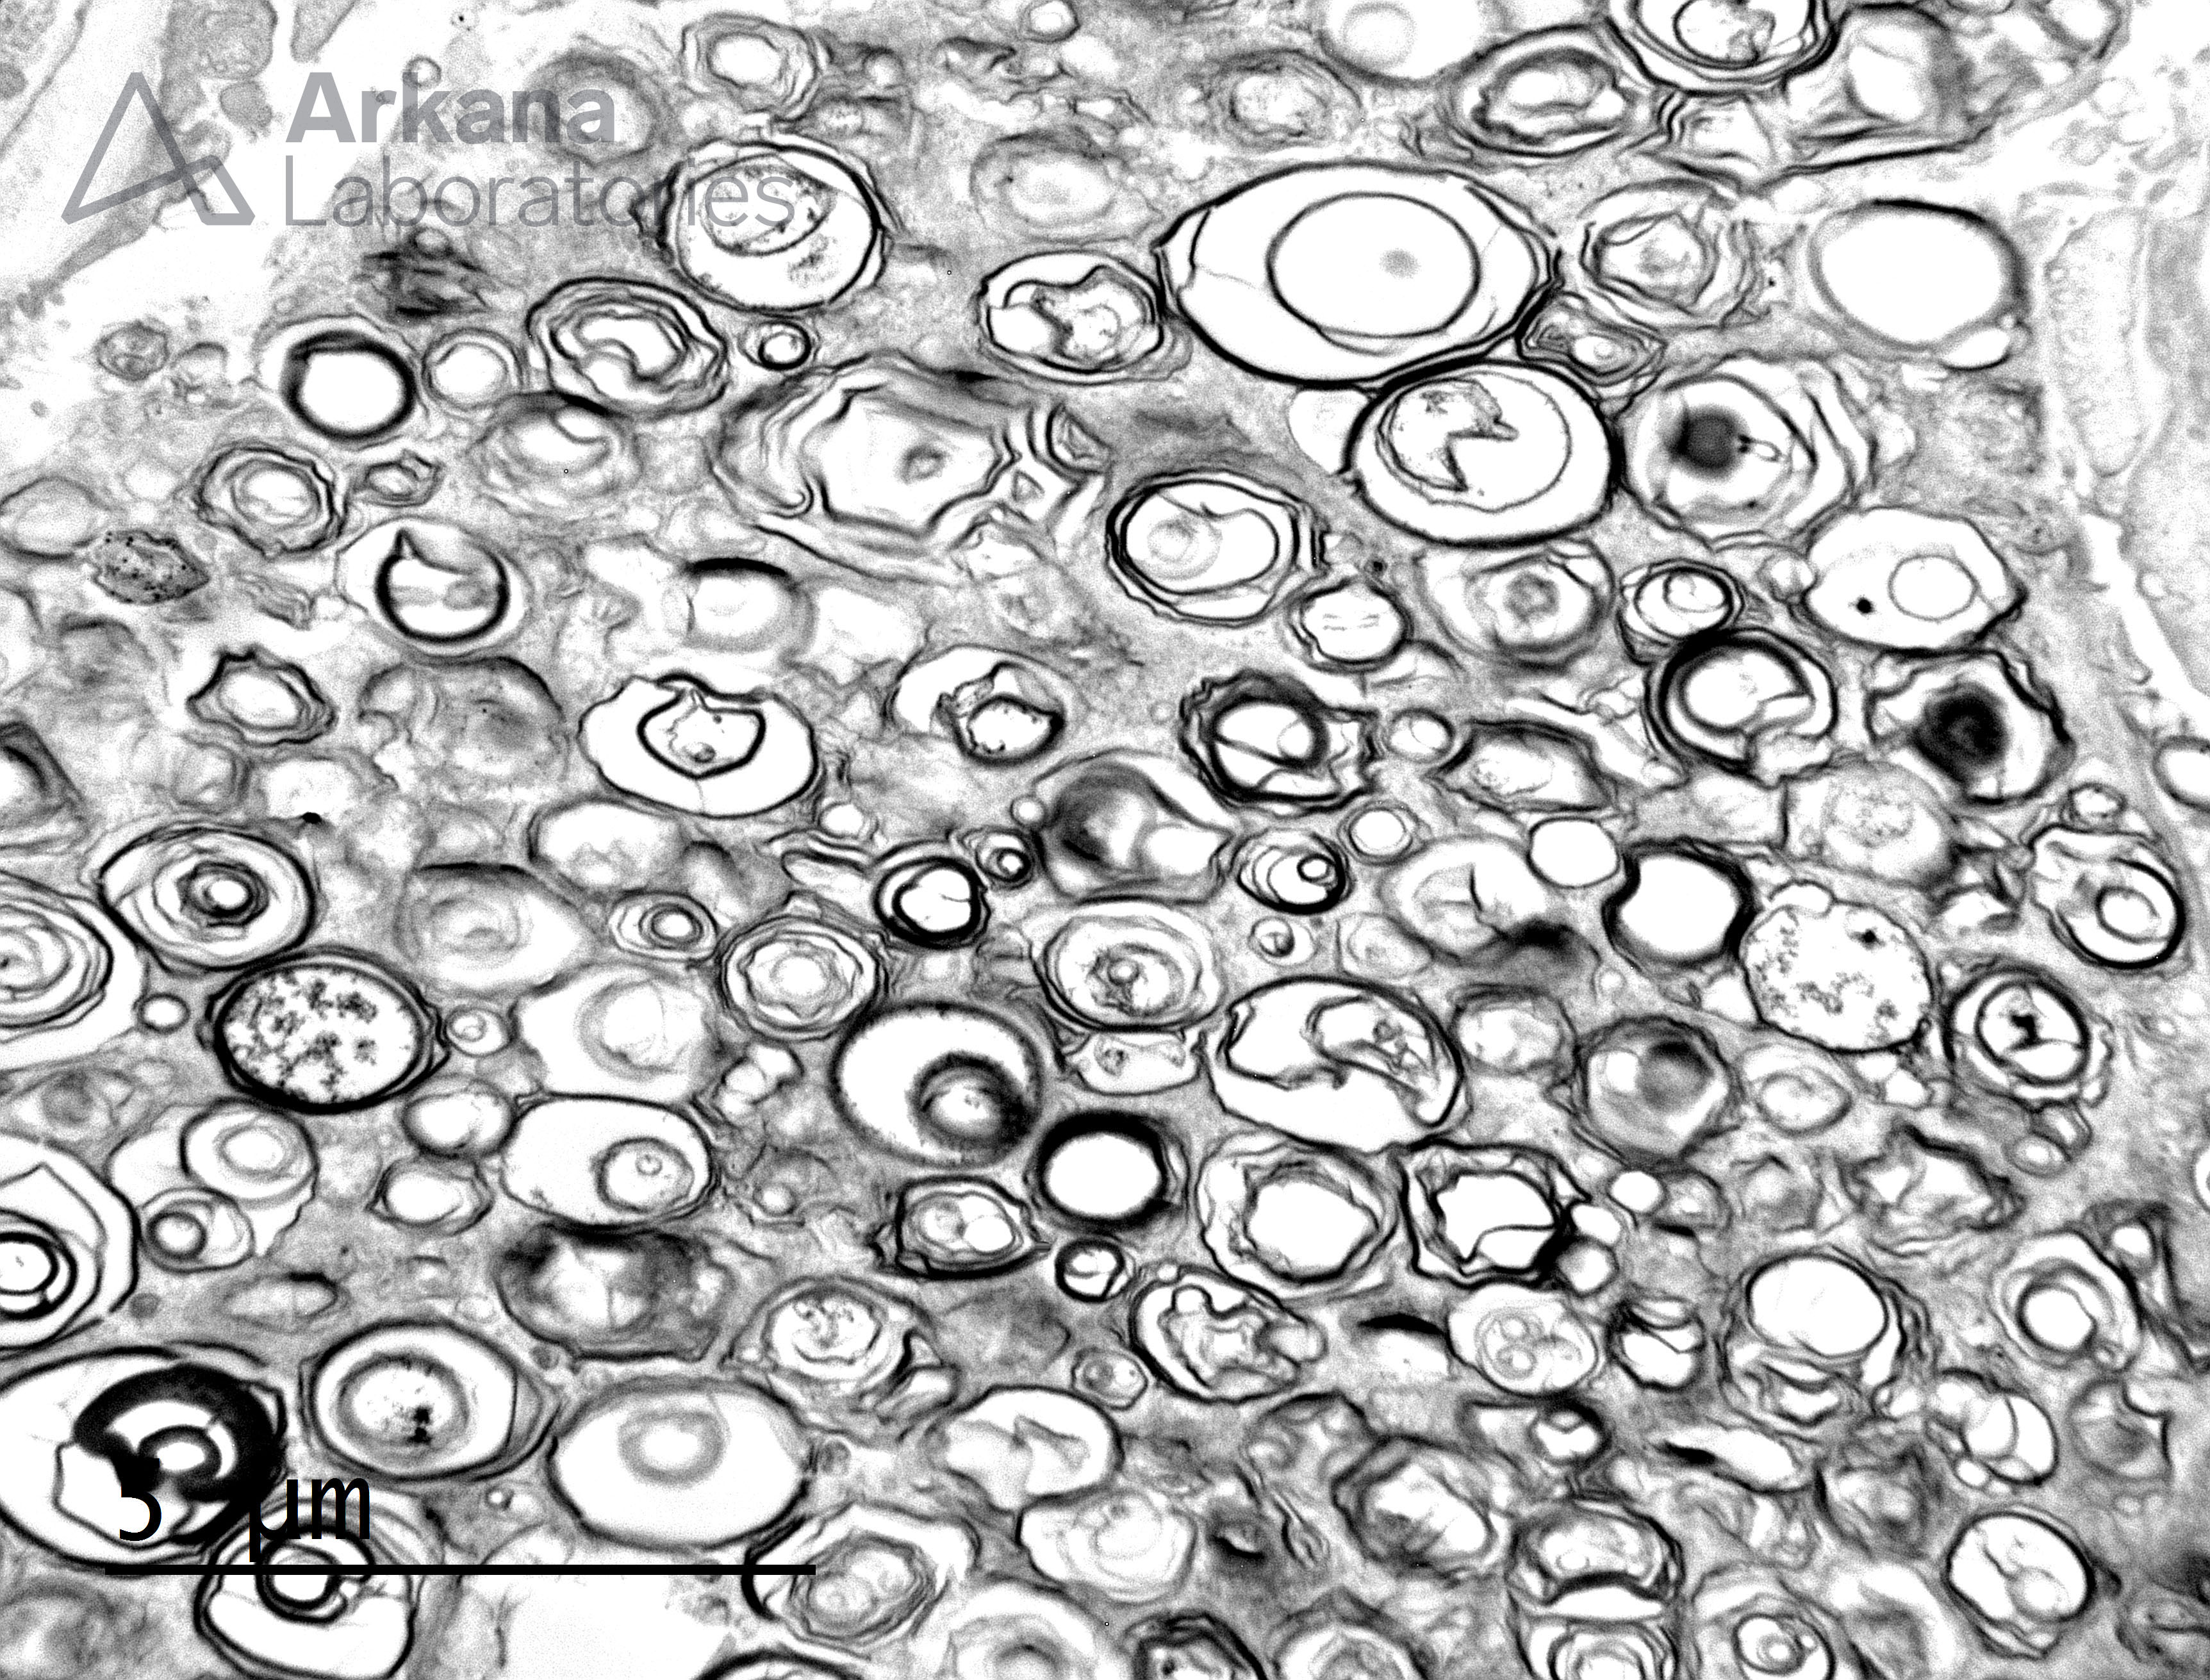

Podocyte Myelin Figures in Fabry Disease